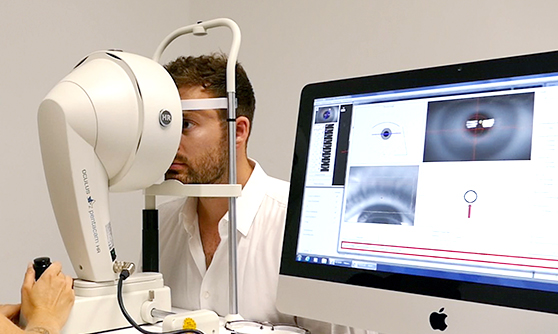

- Messung aller relevanten Augenparameter

- Intensive augenärztliche Voruntersuchung und Vermessung Ihrer Augen

- Messung aller relevanten Augenparameter

- Intensive augenärztliche Voruntersuchung und Vermessung Ihrer Augen